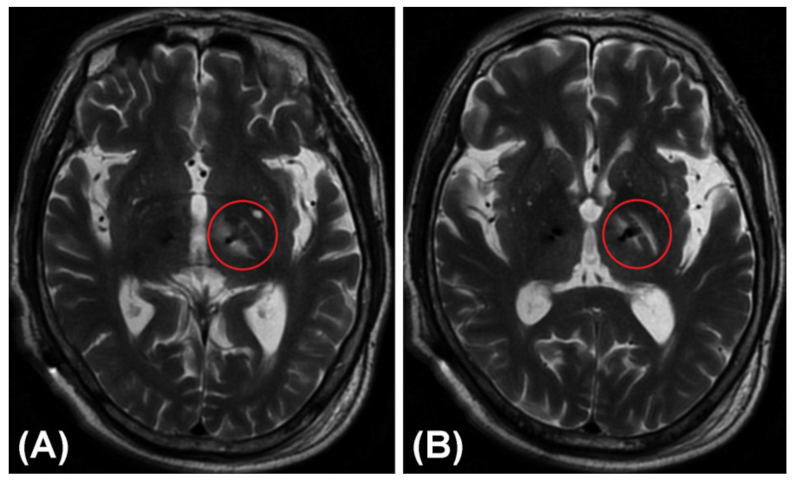

Figure 5 shows a rare non-hemorrhagic edematous lesion around the trajectory in the trajectory planning group. An electrode placed for the left STN through the PLIC led to local edema of the PLIC and adjacent white matter (i.e., the medial medullary lamina), which appeared similar to a “hamburger”, together with the relatively normal GPi. These images were taken from a 71-year-old male patient with PD 3 days after he received bilateral lead placement in the STN. He suffered from transient urinary incontinence and mild weakness of the right limbs after the DBS operation.

Figure 5.

A rare non-hemorrhagic edematous lesion or infarction around the trajectory in a T2-weighted MRI image. An electrode placed for the left STN through the PLIC led to local edema of the PLIC and adjacent white matter (i.e., the medial medullary lamina), which appeared similar to a “hamburger”, together with the relatively normal GPi. (A) Lower layer. (B) Upper layer.